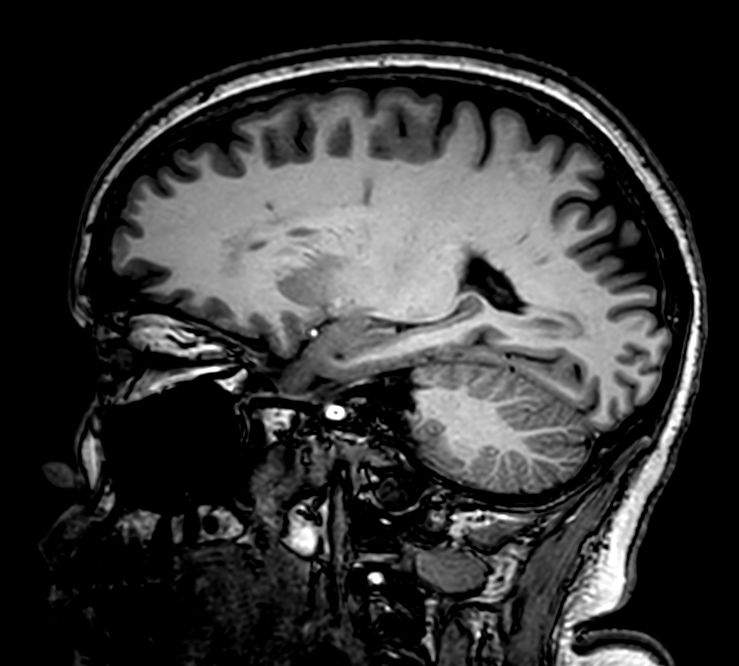

Sagittal 3D VIEW - T1w TSE

Pre-Gado

3D VIEW - T1w TSE (sagittal reformat)

Post-Gado